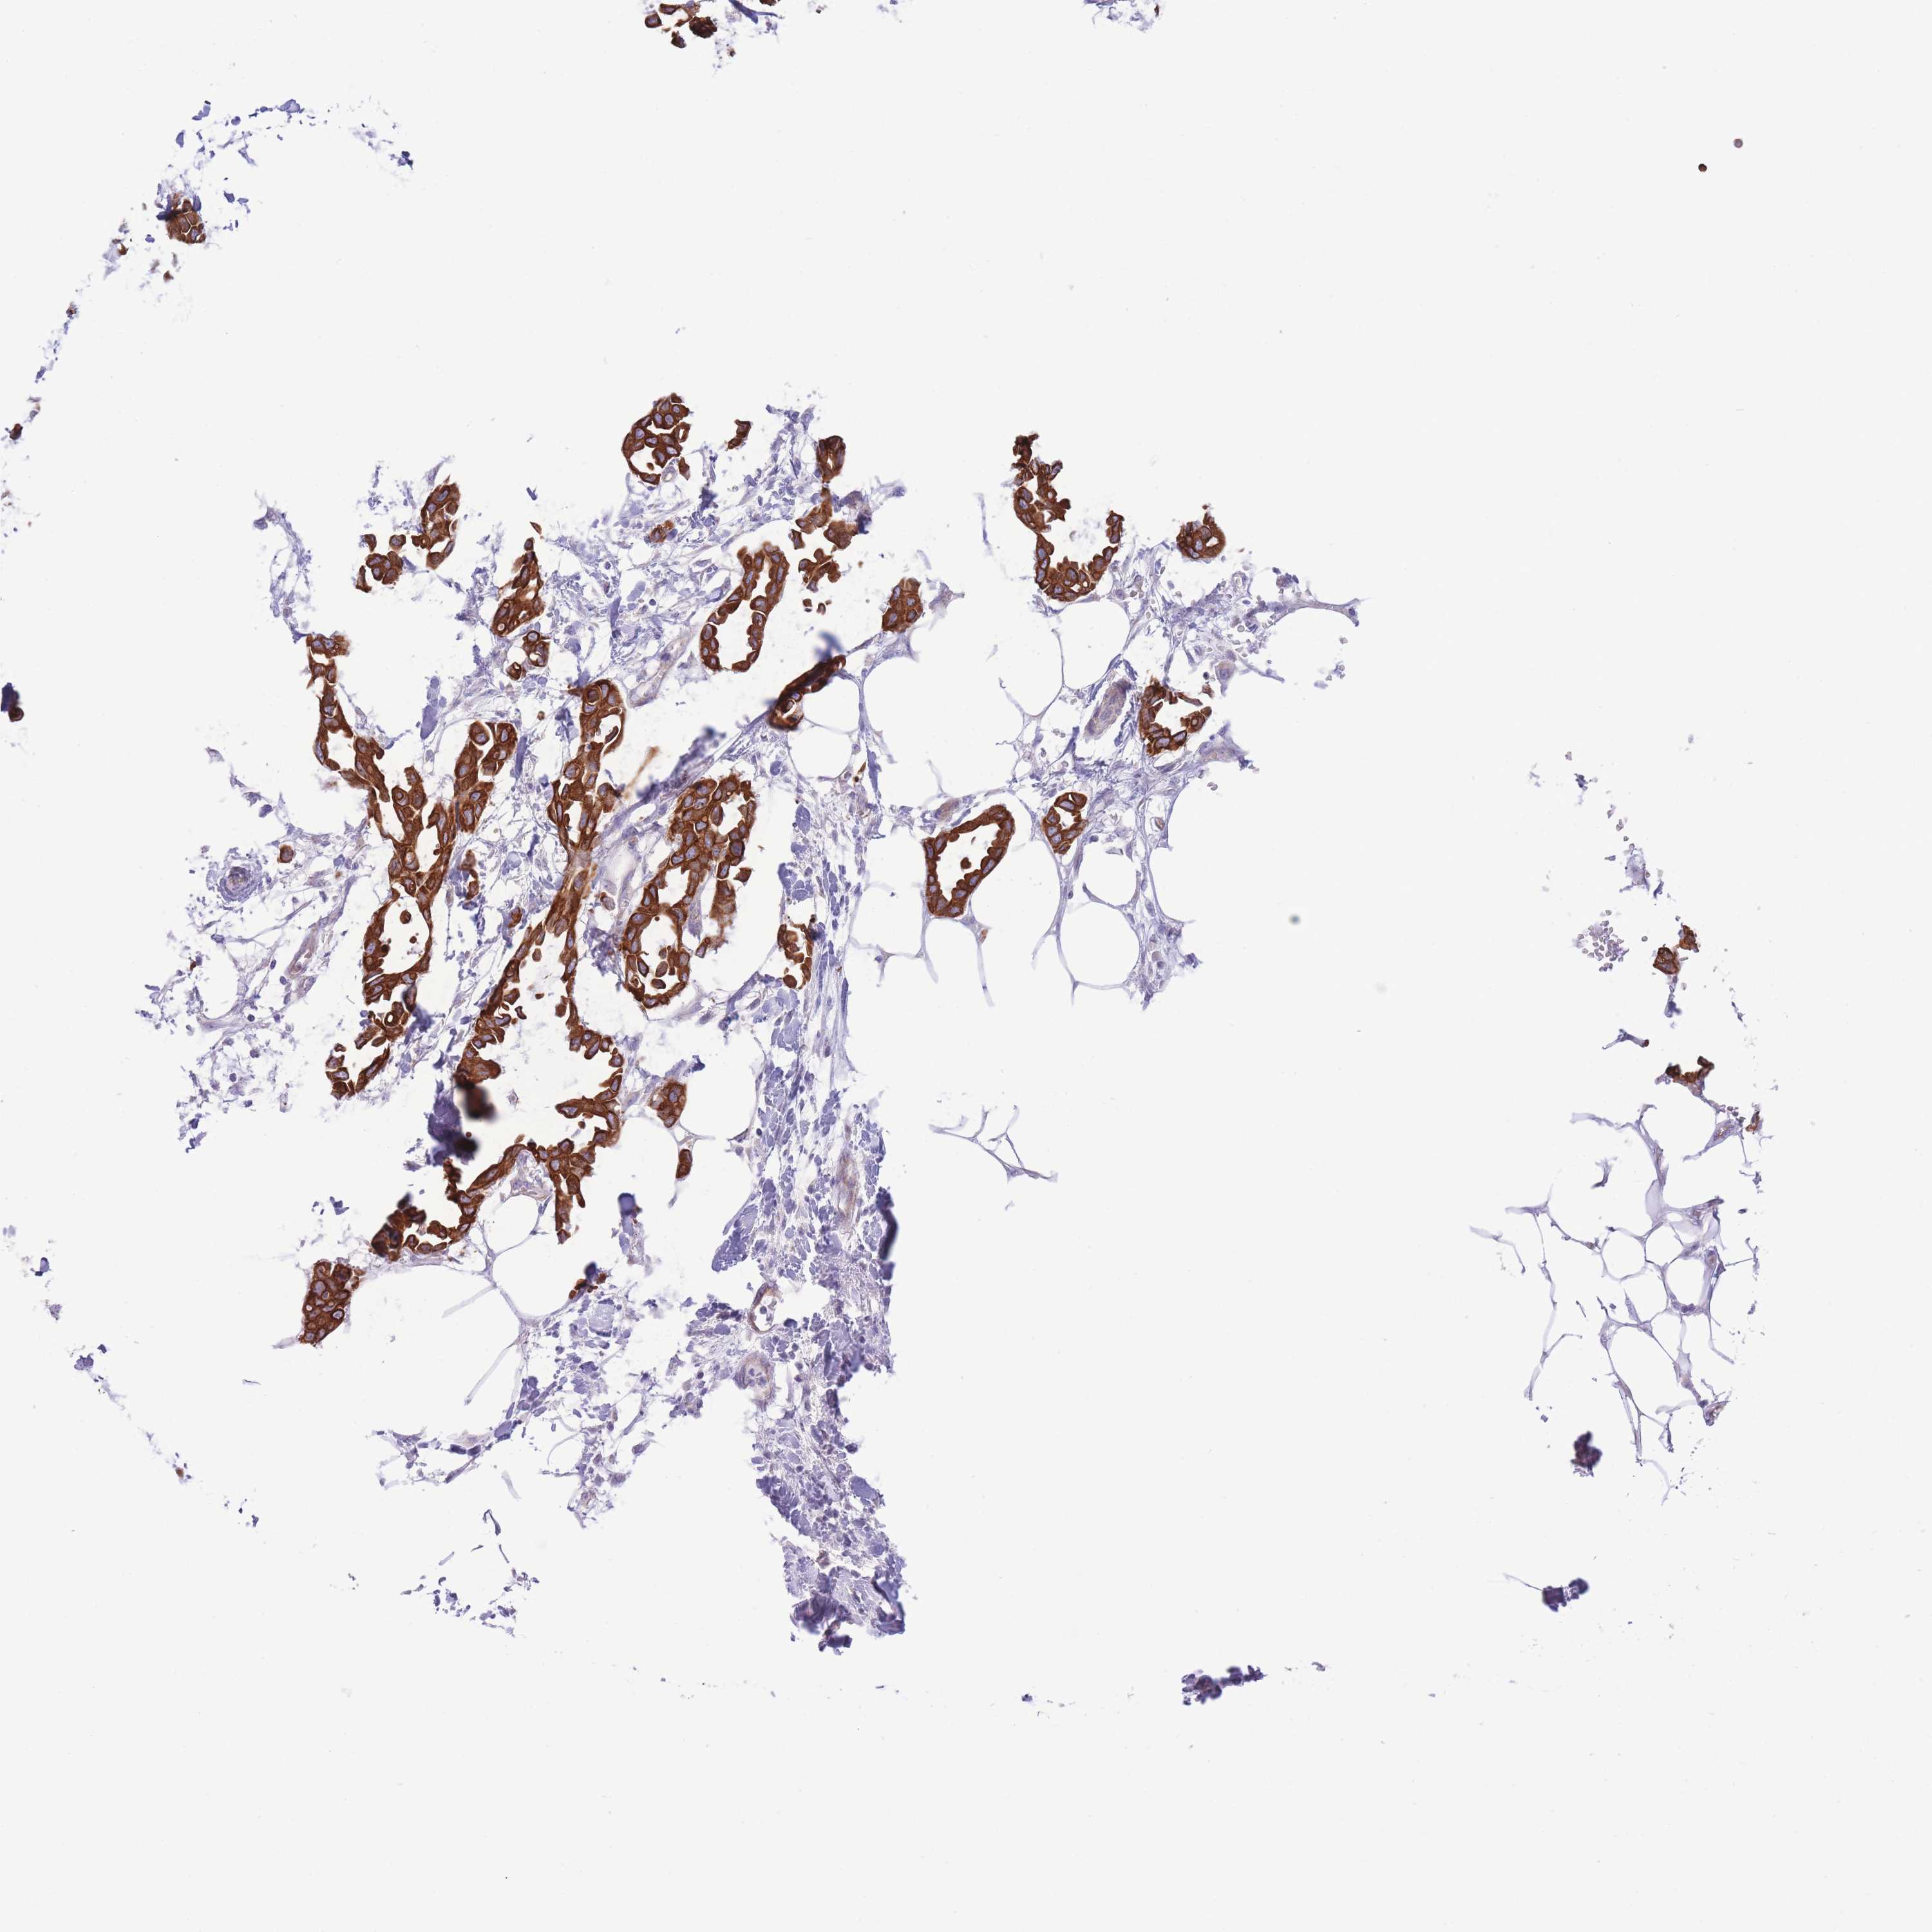

CANCER BREAST CANCER Show tissue menu

BRCA TCGA BRCA VALIDATION PROTEIN EXPRESSION